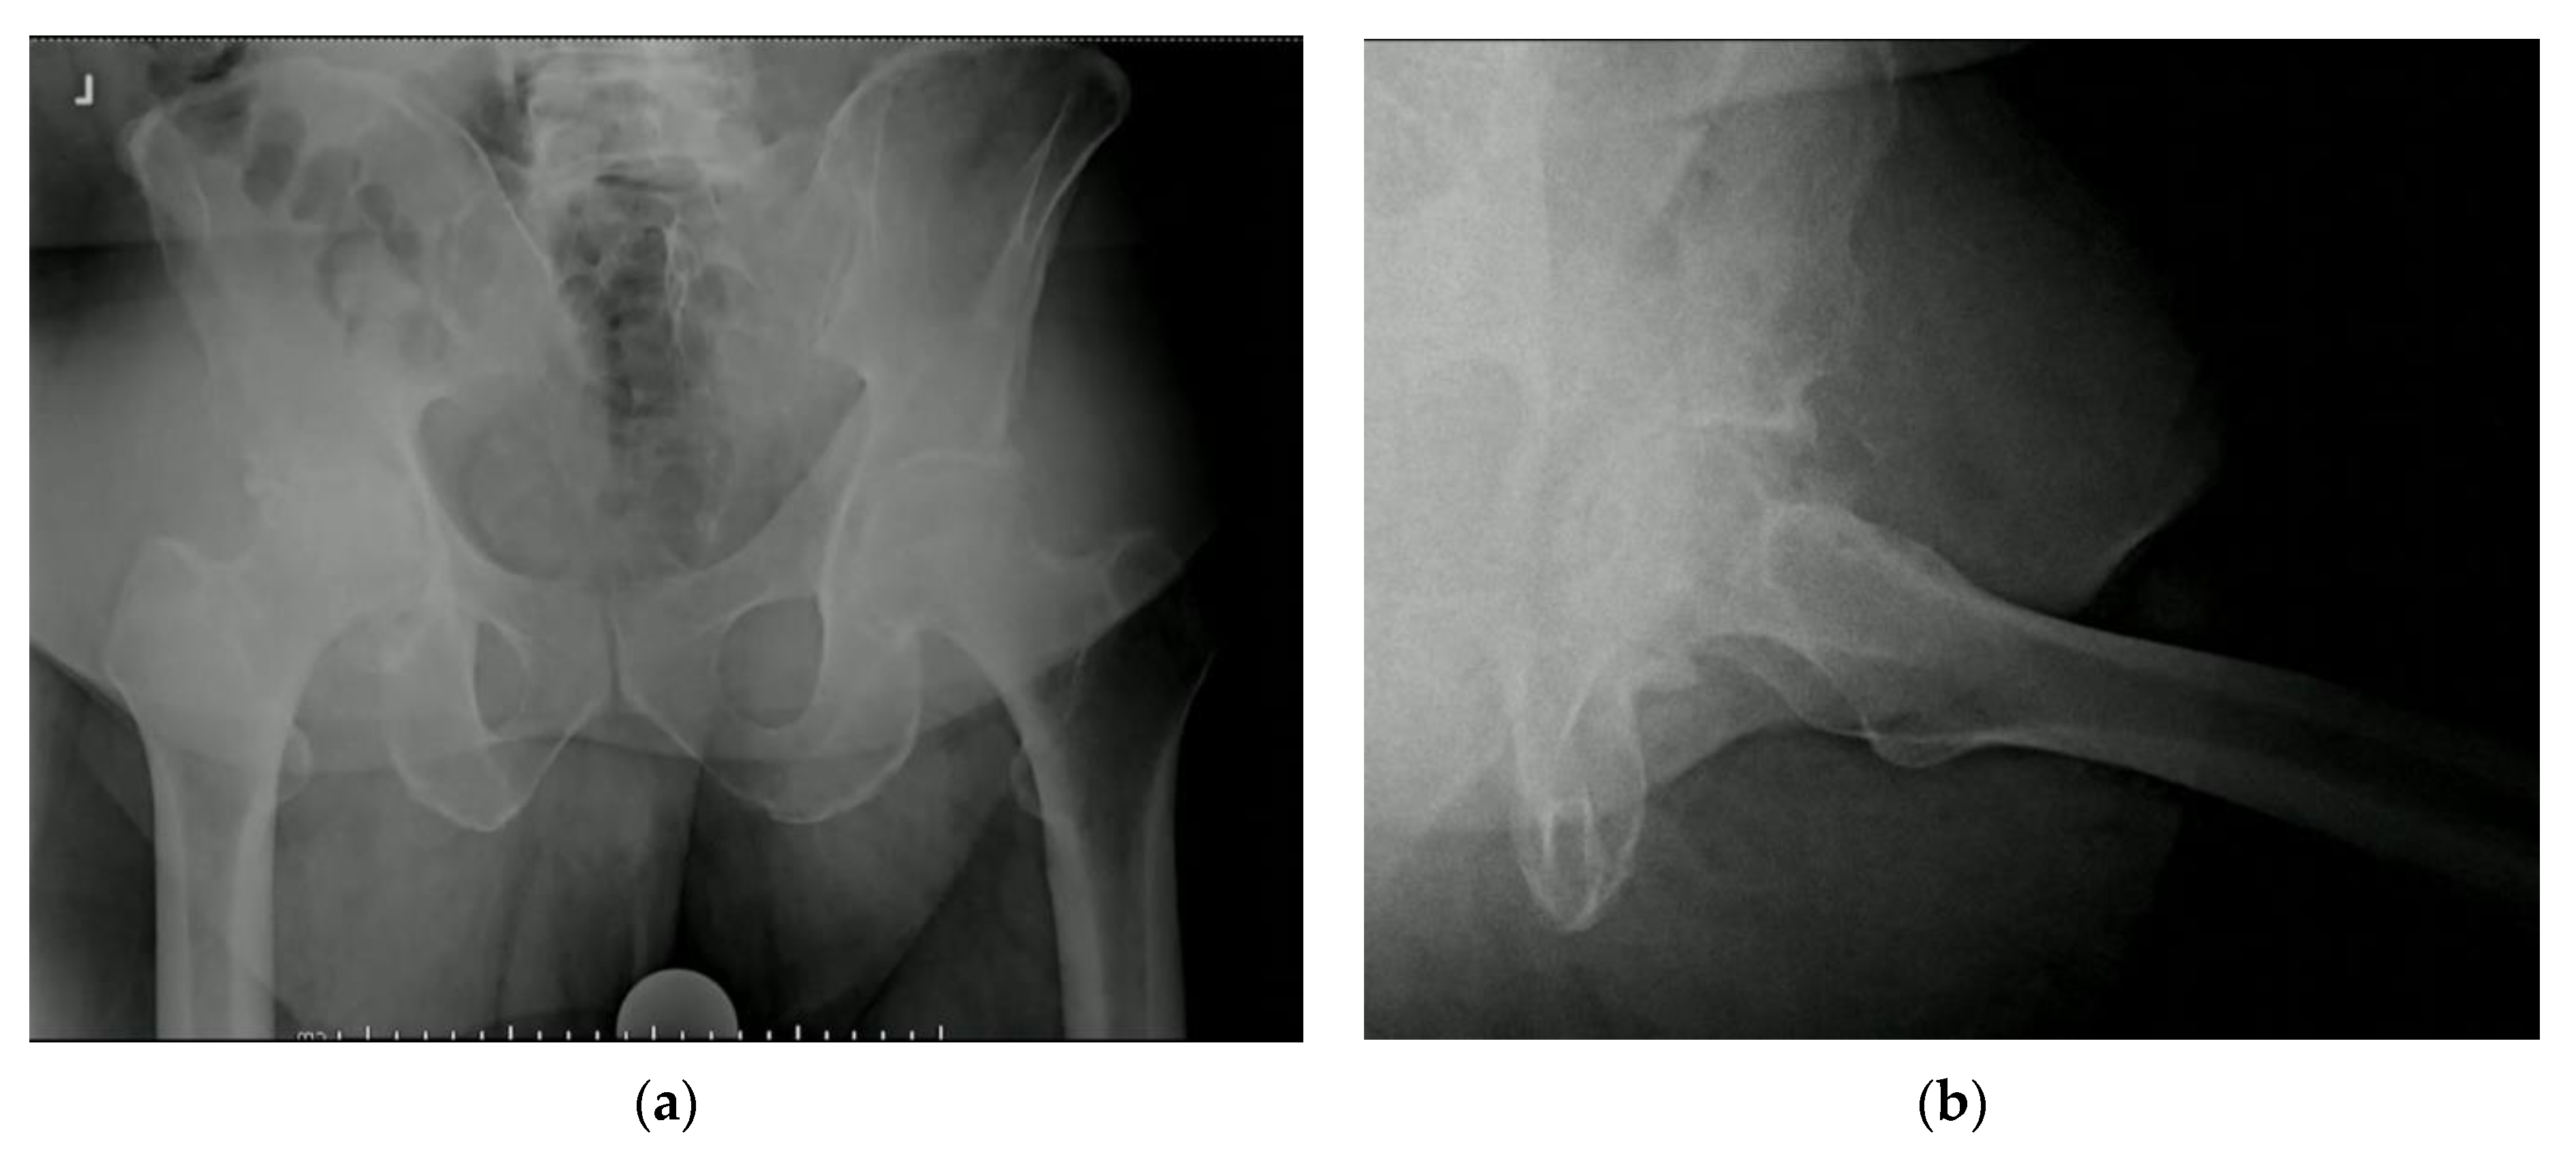

3.3. Protrusio Cases